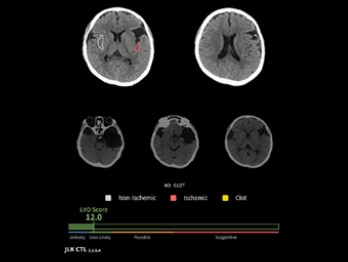

JLK-CTL은 조영제 없이 촬영한 비조영 CT(NCCT) 영상으로 대혈관 폐색(Large Vessel Occlusion, LVO) 여부를 신속하고 정확하게 예측하는 AI 솔루션이다. 응급 현장에서 주로 쓰이는 비조영 CT를 기반으로 조기에 대혈관 폐색 의심 환자를 선별해 골든 타임을 확보하는 것이 핵심이다.

이번 승인은 제이엘케이의 세 번째 혁신의료기기 통합심사 통과 사례로 회사는 앞서 지정을 받은 JBS-01K, JLK-LVO 등과 함께 비조영 CT(컴퓨터단층촬영), CTA(컴퓨터단층조영술), DWI(확산강조영상) 등 뇌졸중 진단에 필수적인 영상 분석에 비급여 처방을 할 수 있는 AI 솔루션 ‘3종 패키지’를 완성하게 됐다.

JLK-CTL을 활용하면 CTA, DWI 등의 정밀검사 대상을 신속하게 선별할 수 있고, 진단 및 치료 결정을 지원해 환자의 예후 개선에 기여할 수 있다. 또 불필요한 검사를 줄일 수 있어 환자의 치료비 부담 완화, 국가 보험재정 절감, 필수의료 체계 강화 등의 긍정적 효과도 기대된다.

제이엘케이 류위선 최고의학책임자는 “JLK-CTL은 대혈관 폐색 가능성을 정량적으로 제시해 의료진이 환자 치료 경로를 빠르게 결정할 수 있도록 지원한다”며 “뇌졸중 AI 솔루션 3종 패키지가 다양한 모달리티(영상 방식)를 지원해 병원 규모나 지역 차이 없이 균일한 분석 결과를 제공하는 등 필수의료 서비스 강화에 도움을 줄 수 있을 것으로 기대한다”고 말했다.